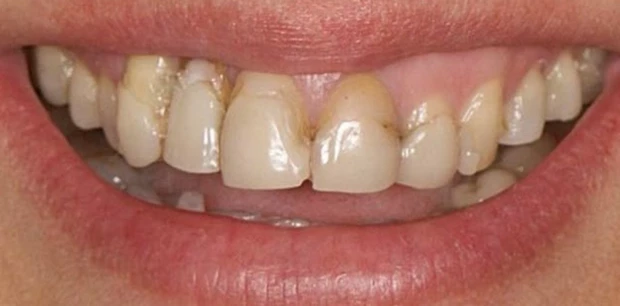

Профгигиена

Профессиональная гигиена полости рта

Выполнено удаление зубного налёта и камня: восстановлен естественный цвет эмали, улучшено состояние дёсен и профилактика воспалений.